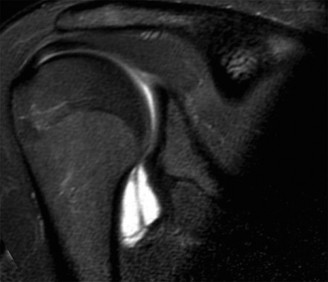

A 35-year-old male has had left shoulder pain for 4 months, ever since a low-speed motor vehicle accident (MV…